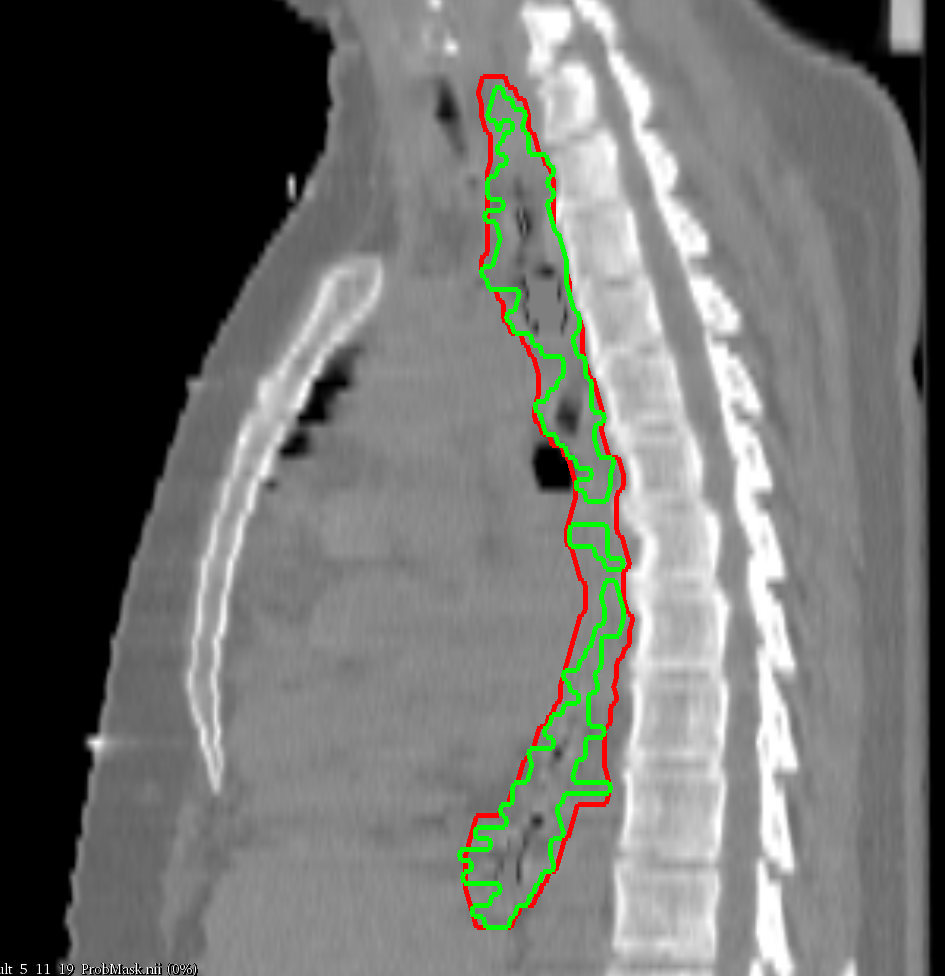

We explored the feasibility of driving a random walk (RW) algorithm Grady (2005) with a CNN and its application to CT esophagus segmentation. Our results prove that a CNN is able to contour the esophagus almost to a perfect extent in some cases (DSC >> 0.9 for clinical cases 09 and 10). However, one can also note that the DSC values for the CNN strongly vary over all cases. Adding a RW for post processing made the performance more homogeneous and, as a whole, increased all figures of merit. The reason why CNN + RW worsened results for some cases is that for those cases the CNN 50 % outline fitted the reference contour already very well and showed very few false positive spots. The RW post processing then enlarged the contour, which resulted in worse figures of merit (an example can be seen in Fig. 6b). The enlargement was due to ”jumps” of the depicted esophagus from one slice to the consecutive ones. As the RW algorithm considers the neighborhood of voxels in all directions it enclosed non-esophageal tissue in those ”jump” areas. Examples can be seen in Fig. 7 and Fig. 5 a–c.

Refer to caption    Refer to caption    Refer to caption

Figure 7: Respiratory motion artifacts with reference contour (green) and generated contour (red).